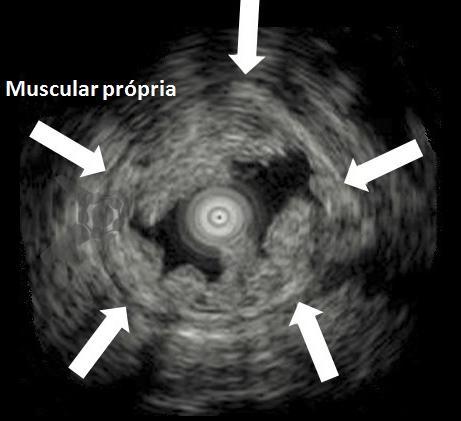

O segredo é um fenômeno chamado redução gravitacional. Ao encher o cólon com água em vez de ar, a flutuabilidade faz a lesão “boiar” para longe da muscular própria, permitindo que a alça capture tecido submucoso adequado sem risco de envolvimento muscular ou perfuração.

Mucosectomia underwater evidenciando flutuação da mucosa e submucosa

Figura 1: Ecoendoscopia evidenciado a mucosa e submucosa ‘flutuando” enquanto a camada muscular se mantém estável. Na UEMR, as lesões flutuam na água por redução gravitacional, permitindo ressecção segura sem envolver a camada muscular.